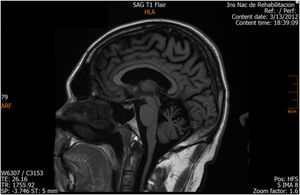

ResultsCase 1 is a 50-year-old male born from a non-consanguineous marriage in Mexico City (Fig. 1A). At age 5, he developed progressive ataxia, dysmetria, cerebellar tremor, and slurred speech. The initial neurological examination revealed bilateral gaze-evoked nystagmus, preserved strength 5/5 except for distal lower limbs (2/5), absent reflexes in all extremities, increased muscle tone in lower limbs, absent Babinski sign, and decreased vibration sensation in lower extremities. Clinical findings are summarized in Table 1. Pes cavus and hammertoes were evident on the last examination at age 47 (Fig. 2); gait was ataxic and only possible with crutches. Brain MRI revealed severe cerebellar and cervical spine atrophy (Fig. 3).

| Patient 1 (Family 1) | M | 47 | 5 | Ataxia, slurred speech, nystagmus, spasticity and decreased vibration sensation in lower extremities, pes cavus and hammertoes | Severe cerebellar and cervical spine atrophy Fig. 3 |